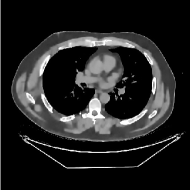

III-B3 Generalization Capability Comparisons between a “Denoising” Deep NN and the Proposed PWLS-ST- Method

This section compares the generalization capabilities between the proposed MBIR method, PWLS-ST-, and a denoising deep NN, FBPConvNet [14], that are trained from the phantom data; in particular, we tested the trained PWLS-ST- and FBPConvNet models to phantom and clinical scan data. The results in Fig. 6 show that the non-MBIR FBPConvNet method has higher overfitting risks, compared to the proposed PWLS-ST- MBIR method. When tested on clinical scan data, PWLS-ST- achieves much more accurate reconstruction, compared to FBPConvNet. See Fig. 6(b). When tested on phantom data, FBPConvNet generates more unnatural features as the number of views reduces, although it gives lower RMSE values compared to PWLS-ST-. See zoom-ins in Fig. 6(a). The FBPConvNet results above correspond to those in the recent work [16] that FBPConvNet [14] generated some unexpected structures.